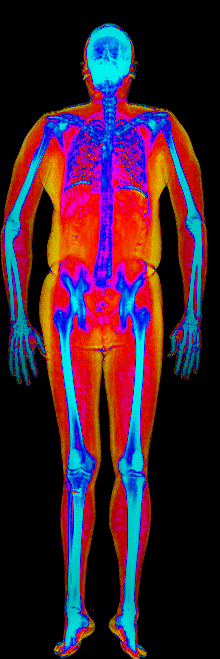

This page features real, anonymized DEXA scan images from BodyStats clients, organized by gender and body fat percentage in 5% increments. DEXA (Dual-Energy X-ray Absorptiometry) is the clinical gold standard for measuring body composition — far more accurate than scales, calipers, or visual estimates.

Each colorized scan shows the distribution of fat tissue (shown in warmer colors) and lean tissue (cooler colors) throughout the body. Compare your own DEXA scan to others in your range, or see what different body fat levels actually look like on a scan.

Male DEXA Scans by Body Fat %

15 to 20% body fat